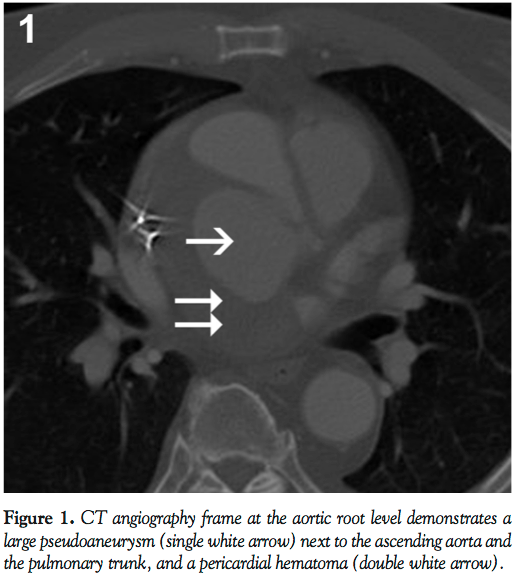

A 69-year-old male underwent a classic Bentall procedure for ascending aortic aneurysm at an outside institution. The patient had done reasonably well until 7 years later when he was admitted to an outside hospital with 2 weeks of fatigue and an episode of exertional dyspnea. Chest computed tomography angiogram revealed a large aortic root pseudoaneurysm at the left main coronary artery with pericardial hematoma (Figure 1). The patient was transferred to our institution for further workup. Aortography performed at our institution